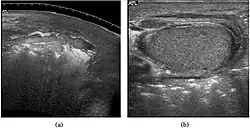

The incidence of infertility is decreased if surgical orchiopexy is carried out before the 1–3 years but the risk of malignancy does not change. Because of the superficial location of the inguinal canal in children, sonography of undescended testes should be performed with a high frequency transducer. At ultrasound, the undescended testis usually appears small, less echogenic than the contralateral normal testis and usually located in the inguinal region [Fig. 29]. With color Doppler, the vascularity of the undescended testis is poor.

-

Fig. 29. Undescended testis. (a) Normal testis in the scrotum. (b) Atrophic and decreased echogenicity of the contralateral testis of the same patient seen in the inguinal region.